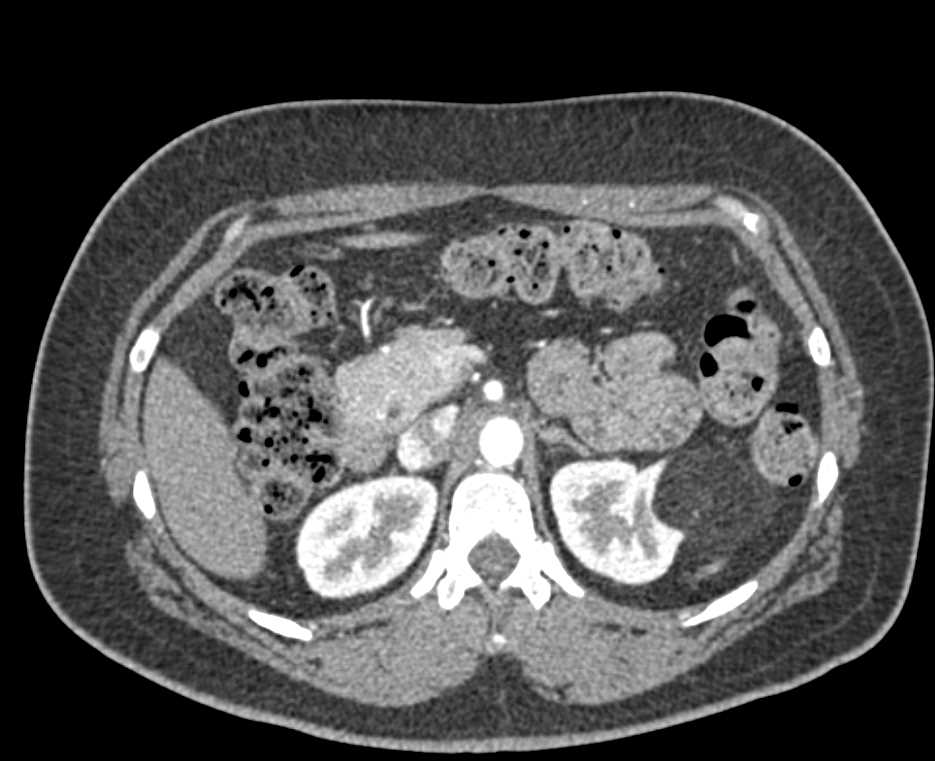

Renal Cell Carcinoma Right Kidney